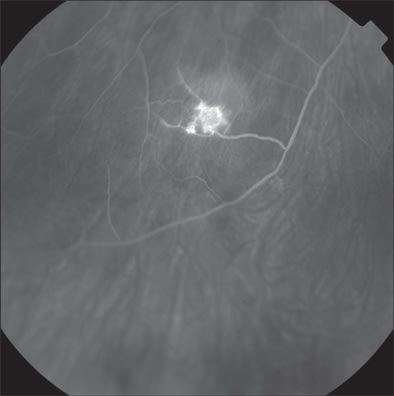

Ophthalmologic examination demonstrated a corrected visual acuity of 20/20 in each eye and the patient correctly identified 11/11 Ishihara color plates. Pupils were briskly reactive without any afferent defect. Slit-lamp examination of the anterior segment was unremarkable. Dilated funduscopic examination showed 3 midperipheral endophytic retinal hemangiomas in the right eye and 1 peripheral hemangioma in the left eye. Fluorescein angiography confirmed the presence of these retinal hemangiomas.

Figure 9. Midphase fluorescein angiography showing retinal hemangiomas in the right eye.

Figure 10. Another midphase fluorescein angiography showing retinal hemangiomas in the right eye.